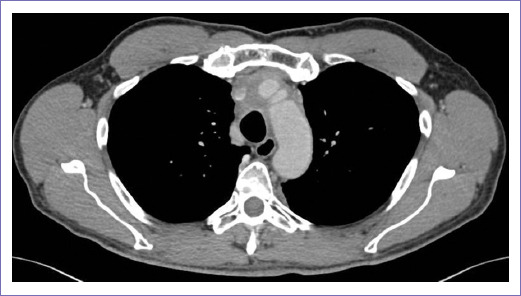

En junio y octubre de 2022 se realizan TC de tórax, que se reportan como enfermedad estable (Figs. 5 y 6). En noviembre de 2022 presentó mejoría en patrón de actividad física, persistiendo disnea de grandes esfuerzos. Hasta esta valoración, sin síntomas de neumonitis. A la exploración física, se encontró sin alteraciones en signos vitales, con peso corporal de 80 kg y KPS del 80%. Sin datos de red venosa colateral. Por presentar adecuada evolución clínica con esquema de radioterapia hipofraccionada, se planeó continuar seguimiento estrecho.

En cuanto a las características por imagen, las imágenes de cortes transversales mediante TC, resonancia magnética y ultrasonografía permiten la identificación de diferentes elementos dentro de estos tumores, incluidos los tejidos blandos, los líquidos, la grasa y el calcio. En este paciente, mediante TC, se documentó un tumor mediastinal en el compartimento anterior, con densidad de tejidos blandos, en los cuales se apreció mayor involución tumoral tras el tratamiento con radioterapia, así como calcificaciones gruesas envolviendo al tronco braquiocefálico derecho, carótida común izquierda y subclavia ipsilateral con calcificaciones gruesas localizadas en el espacio prevascular, características propias de los teratomas maduros reportadas ampliamente en la literatura, a excepción del componente quístico, que en nuestro paciente no se documentó13.